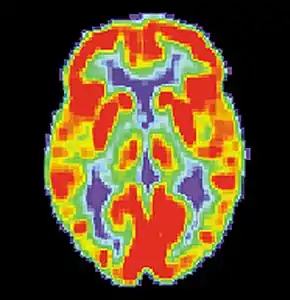

برش نگاری مغز با گسیل پوزیترون یک شکل از برش نگاری با گسیل پوزیترون (PET) است که برای اندازه گیری متابولیسم مغز و توزیع عوامل شیمیایی بیرونی نشان دار شده با ماده رادیواکتیو در سراسر مغز استفاده می شود. PET میزان گسیل مواد شیمیایی فعال متابولیکی نشان دار شده با ماده رادیواکتیو را که به جریان خون تزریق شده اند، اندازه گیری می کند. داده های خروجی برش نگاری مغز با گسیل پوزیترون، توسط رایانه پردازش می شود تا تصاویری چند بعدی از توزیع مواد شیمیایی در مغز تولید شود.[1]

![]() اسکن برش نگاری با گسیل پوزیترون از یک مغز عادی | |